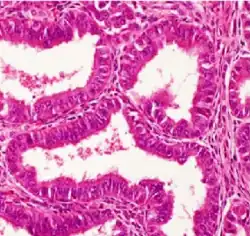

Histopathology of a well-differentiated endometrioid adenocarcinoma in the ovary

Light microscopy shows tubular glands, resembling endometrium.[8]